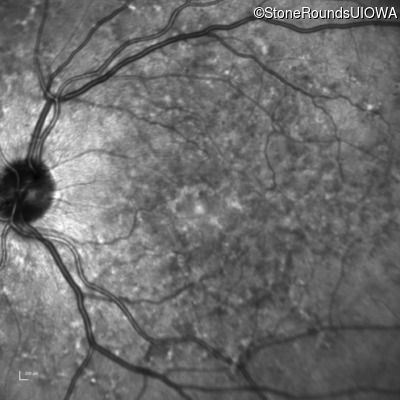

Infrared Fundus Photograph - Right - 20/25 -2

Exemplar